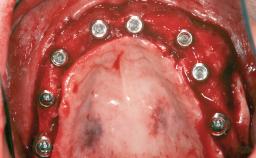

A 47-year-old Caucasian woman with a single-tooth edentulous space at the site of the left maxillary canine was referred for treatment. She had undergone traumatic extraction of this impacted canine several months before referral. Her chief complaint was the dissatisfying appearance of her smile. The patient desired a stable and esthetic rehabilitation of the site. Her dental history showed no evidence of periodontal disease or bruxism. She had no systemic diseases, was not taking any medications, and did not smoke. The extraoral examination revealed a high lip line and an inadequate soft-tissue volume at the defective canine site. Large black triangles were visible between the canine and its adjacent teeth.